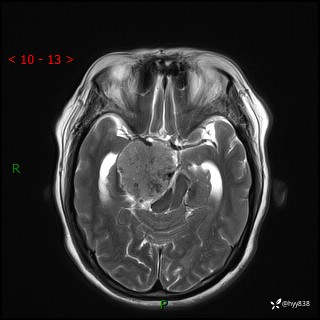

颅脑MRI平扫+增强